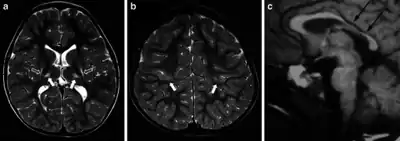

| MR images in a boy with dyskinetic cerebral palsy who has neuroimaging findings of acute profound hypoxic–ischaemic brain injury | |

Around 70% of patients with DCP show lesions in the cortical and deep grey matter of the brain, more specifically in the basal ganglia and thalamus. However, other brain lesions and even normal-appearing MRI findings can occur, for example white matter lesions and brain maldevelopments.[3][15][17][18] Patients with pure basal ganglia and thalamus lesions are more likely to show more severe choreoathetosis whereas dystonia may be associated with other brain lesions, such as the cerebellum.[3] These lesions occur mostly during the peri- and postnatal period since these regions have a high vulnerability during the late third trimester of the pregnancy.[19] Unfortunately, contemporary imaging is not sophisticated enough to detect all subtle brain deformities and network disorders in dystonia. Research with more refined imaging techniques including diffusion tensor imaging and functional MRI is required.[8][20]